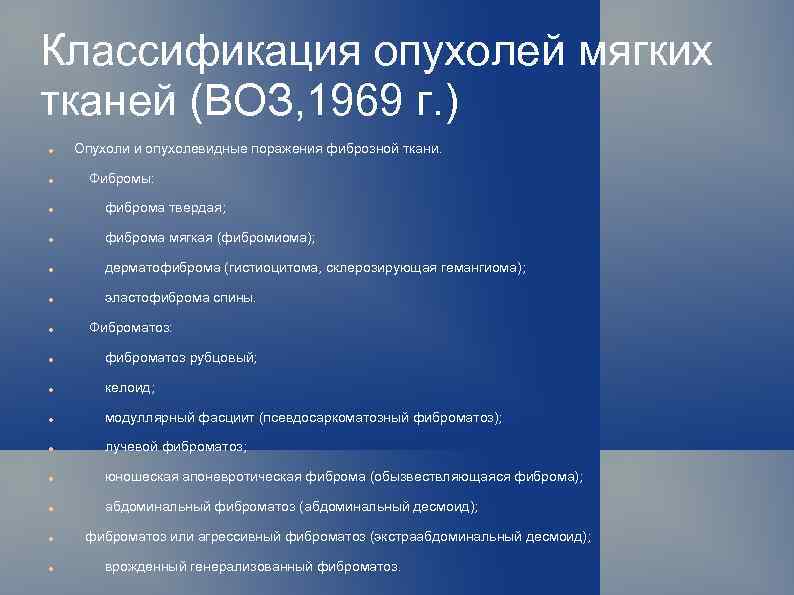

Классификация опухолей мягких тканей (ВОЗ, 1969 г. ) Опухоли и опухолевидные поражения фиброзной ткани. Фибромы: фиброма твердая; фиброма мягкая (фибромиома); дерматофиброма (гистиоцитома, склерозирующая гемангиома); эластофиброма спины. Фиброматоз: фиброматоз рубцовый; келоид; модуллярный фасциит (псевдосаркоматозный фиброматоз); лучевой фиброматоз; юношеская апоневротическая фиброма (обызвествляющаяся фиброма); абдоминальный фиброматоз (абдоминальный десмоид); фиброматоз или агрессивный фиброматоз (экстраабдоминальный десмоид); врожденный генерализованный фиброматоз.